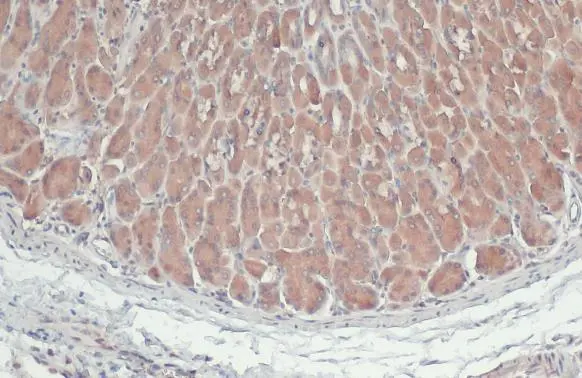

ApplicationsWestern Blot, ImmunoHistoChemistry, ImmunoHistoChemistry Paraffin

- ApplicationsWestern Blot, ImmunoHistoChemistry, ImmunoHistoChemistry Paraffin